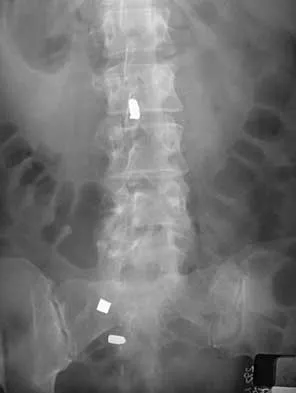

An otherwise healthy 70-year-old man has back and bilateral leg pain in an L5 distribution that is aggravated by standing more than 10 minutes or walking more than 100 feet. He has to sit to get relief. Neurologic and pulse examinations are normal. A radiograph and MRI scan are shown in Figures 4a and 4b. Treatment should consist of

Explanation

The patient has a degenerative spondylolisthesis at L4-5 with associated spinal stenosis. His symptoms are consistent with neurogenic claudication. Based on these findings, the surgical treatment of choice is decompression and posterolateral fusion. Use of instrumentation is controversial. Laminectomy alone is reserved for the patient who is frail medically. There is no role for an anterior approach or for fusion alone without decompression. Fischgrund JS, Mackay M, Herkowitz HN, et al: Degenerative lumbar spondylolisthesis with spinal stenosis: A prospective, randomized study comparing decompressive laminectomy and arthrodesis with and without spinal instrumentation. Spine 1997;22:2807-2812.